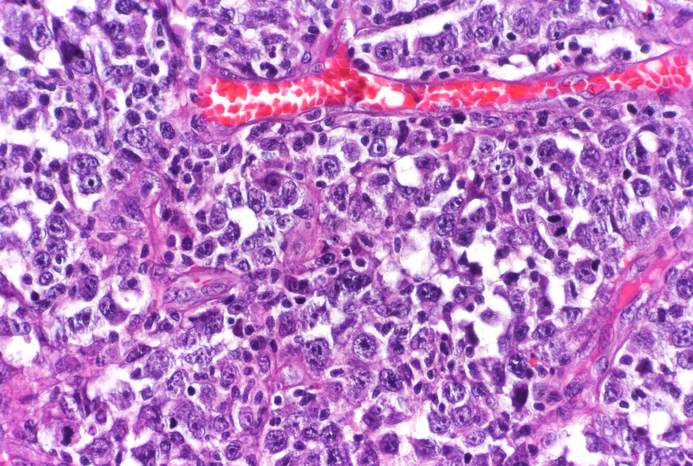

The study, published April 20 in Cancer Discovery, found that having a mutation in one of the two copies of SETD2 in B cells can lead to a proliferation of cells that don’t readily repair their mutated DNA, causing an aggressive type of cancer called diffuse large B cell lymphoma (DLBCL).

Diffuse large B cell lymphoma develops in B cells in the lymph nodes of humans, dogs and some other mammals. To understand the underlying causes, lead author Dr. Wilfred Leung examined B cells of mice genetically engineered to lack one copy of SETD2. He began the study as a doctoral candidate in the laboratory of Dr. Kristy Richards, who was an associate professor with a joint appointment at the College of Veterinary Medicine at Cornell University and Weill Cornell Medicine. Her laboratory had studied cancer in humans and canines to accelerate the development of potential new treatments. Dr. Leung joined Dr. Melnick’s laboratory to complete the work after Dr. Richards died of breast cancer in 2019.